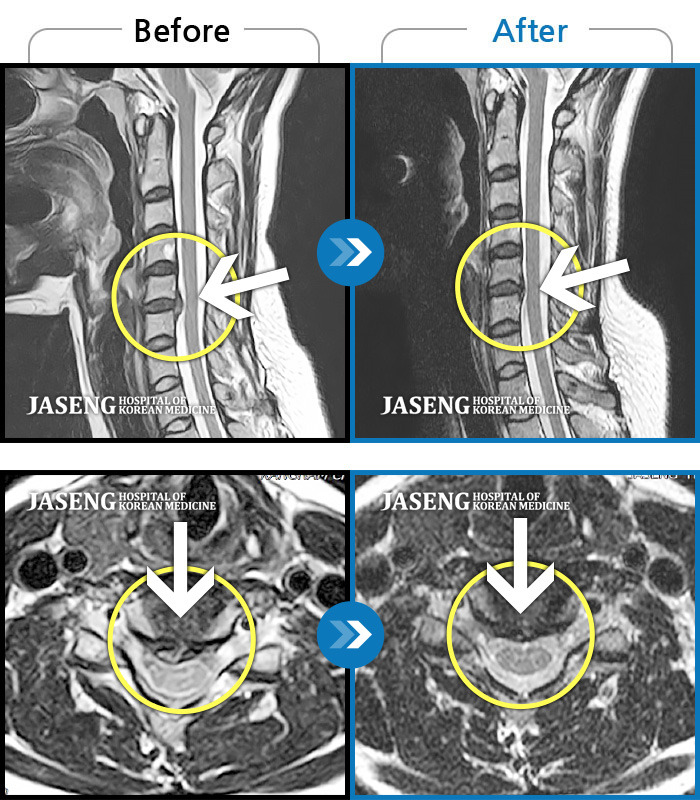

4. MRI 결과와 현재 증상이 맞아떨어질 때

MRI 결과를 처음 봤을 때는 무섭기보다 낯설었습니다.

하지만 시간이 지나며 한 가지가 분명해졌습니다.

- MRI에 나온 위치

- 내가 느끼는 저림의 위치

- 불편한 손과 손가락

이 세 가지가 점점 정확히 겹치기 시작했습니다.

이때부터 MRI는 종이가 아니라 거울처럼 느껴졌습니다.